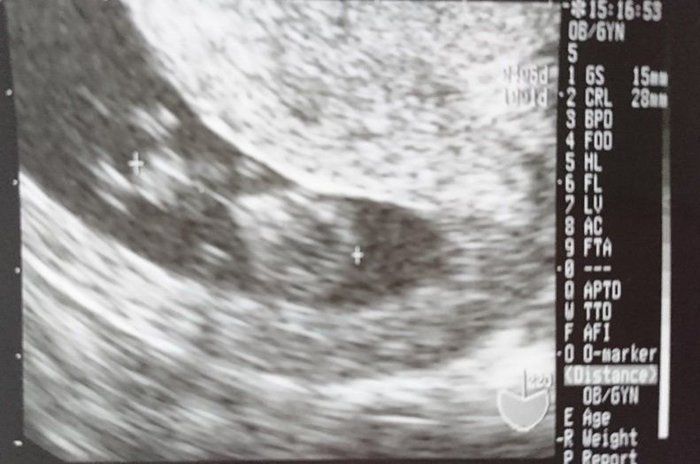

小吉さんの妊娠9週目のエコー写真

赤ちゃんは2.8cmになりました。ハート型のように写っている胎嚢の右側にあるのが頭で左側が体です。人間らしくなってきたのが嬉しかったのを覚えています。マクロビオティックの先生からいただいたアドバイスを元に、食事内容や体を冷やさないことなどに注意をしながら慎重に毎日を過ごしていました。